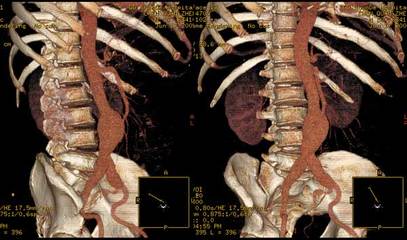

4. 4. 3 CT 血管造影 (CTA) CTA 创伤小 , 费用低 , 可以准确测量腹主动脉瘤各项数据 , 已经基本替代经导管血管造影。特别是近年来出现的多排 CT, 可以在更短的时间里得到更多的高质量图像 , 进一步提高 CT 诊断的准确率。在一些医学中心 CTA 已经逐渐成为腹主动脉瘤术前检查和术后随访的金标准。腹主动脉瘤术前 CT 评估内容包括 :瘤体最大直径 ; 瘤体和肾动脉的关系 ; 肾动脉下正常主动脉( 即瘤颈 ) 的长度、直径及成角、钙化情况 ; 髂动脉的直径及迂曲情况 ; 还需要仔细分析有无血管变异 , 如副肾动脉、双下腔静脉或主动脉后左肾静脉等。所有这些数据都可通过一次高质量的 CTA 了解清楚。